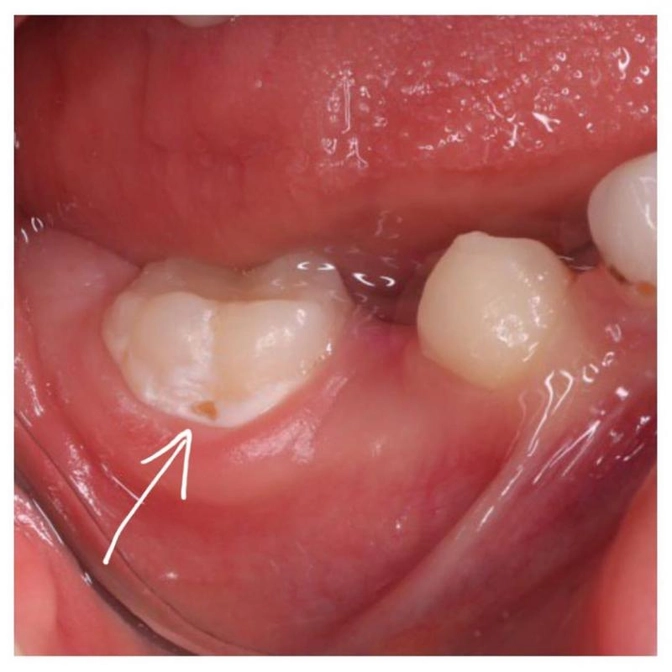

Мальчику 8 лет, он наш постоянный пациент.

Снова отвратительная гигиена, которая стала причиной серьезного воспаления десны.

К этому привело большое скопление мягкого зубного налета в области "шестерки" на нижней челюсти.

Налет собирается преимущественно в придесневой области зуба и под ним начинает свое разрушительное действие кариес.

Сначала это было просто пятно, а теперь возле десны уже "дырочка".

Это поверхностный кариес, его нужно лечить, чтобы спасти зуб.